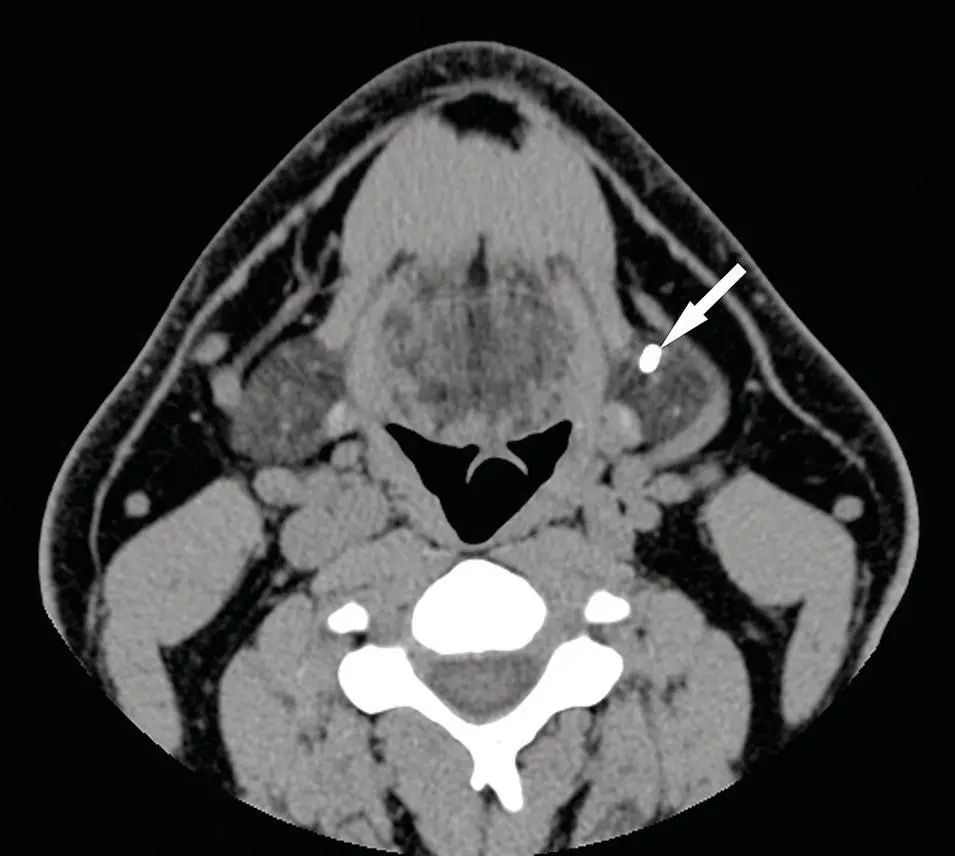

Figure 2.2. Axial CT of the neck in soft‐tissue window with IV contrast demonstrates improved visualization of structures with enhancement of tissues and vasculature. Note the small lipoma (arrow) anterior to the left submandibular gland, which distorts the anterior aspect of the gland with slight posterior displacement.